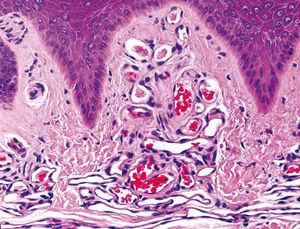

Realizamos una biopsia de la lesión y en el estudio histopatológico destacaba, bajo una epidermis conservada, una proliferación de vasos capilares agrupados en ovillos, con estroma laxo, localizados en las papilas dérmicas (figs. 2 y 3). En el resto de la dermis no existía infiltrado linfocitario ni ningún otro hallazgo patológico. La inmunotinción con CD 31 resultó positiva para las células endoteliales (figs. 4 y 5).

Figura 3. Detalle de la proliferación de vasos capilares agrupados en ovillos, con estroma laxo. Hematoxilina-eosina, 60.